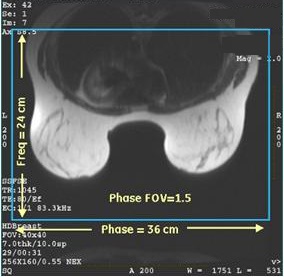

- There are occasions when a “memory not enough, please reduce the scan size” message appears. This most frequently occurs with bilateral multi-phase scans. If this occurs, reduce scan parameter values that affect image size and, therefore, affect the memory required for acquisition (number of phases, slices, matrix size, or Zero-fill Interpolation Processing factor). Alternatively, the Phase FOV > 1 scan parameter can be modified to reduce matrix size without sacrificing resolution but reducing memory consumption. For example, both of the following scan parameters result in a 1 mm2 resolution:

- Freq= 240 and Phase=240 with FOV=24 cm and Phase FOV=1.5

Figure 5. VIBRANT with Phase FOV = 1.5

- Freq= 360 and Phase=360 with FOV=36 cm and Phase FOV=1.0